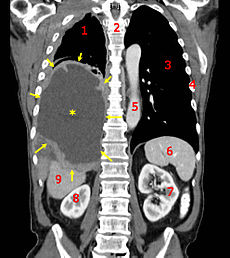

![]() A coronal CT scan showing a malignant mesothelioma Legend: → tumor ←, ✱ central pleural effusion, 1 & 3 lungs, 2 spine, 4 ribs, 5 aorta, 6 spleen, 7 & 8 kidneys, 9 liver. |